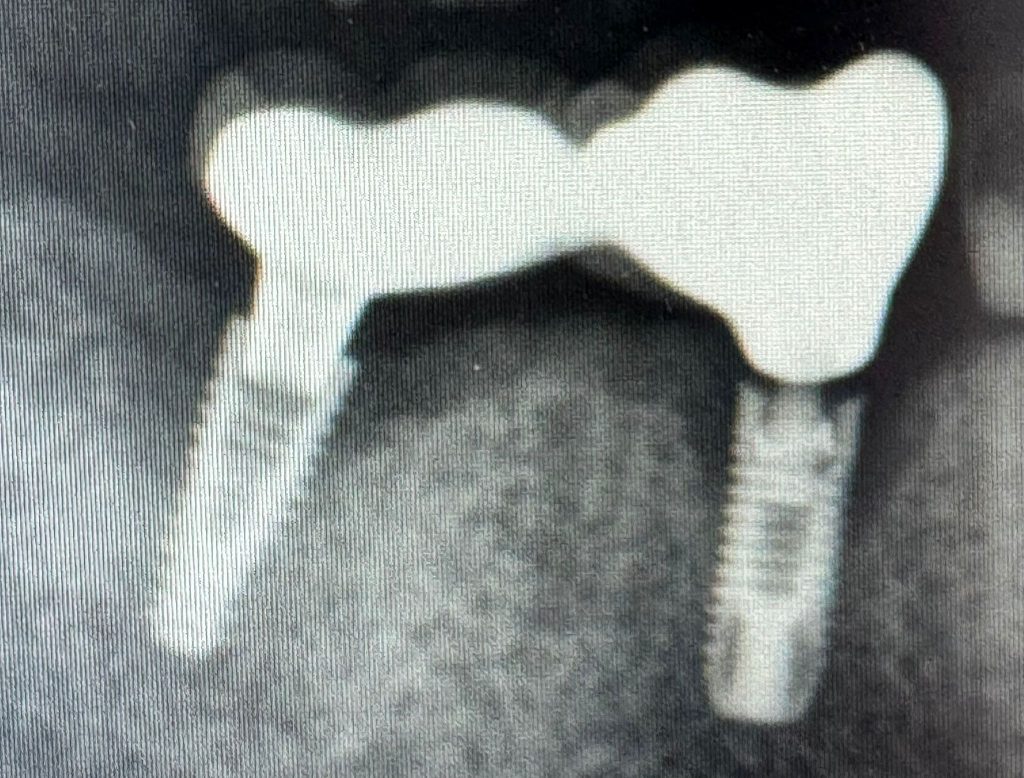

Osteoimplant y Osteoimplant Complex: apoyo decisivo en enfermedad periimplantaria, recesión y pérdida de estabilidad antes de la explantación Durante años se ha asumido casi como dogma que los implantes dentales sufren una pérdida ósea anual inevitable, vinculada al tiempo. Sin embargo, la evidencia más reciente abre un debate necesario: ¿es realmente el paso de los […]